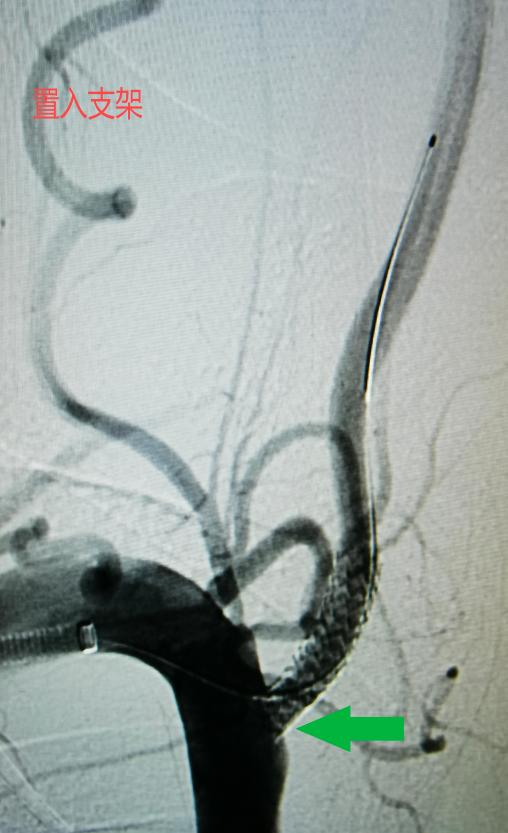

手术过程中,血管外科执行主任李鑫使用如头发丝粗细的导丝迅速通过病变段狭窄建立治疗轨道,沿着这根轨道将一枚精细的血管支架精准无误地放置在病变部位的血管,使得之前闭塞了80%的管腔恢复到了正常的血液供应水平。整个手术过程不到半小时,而唯一的“创伤”就是右手肘部的一个小小针眼。术后,王大叔的头晕、头疼及黑矇等症状均得到了明显缓解,生活质量得到了显著提高。